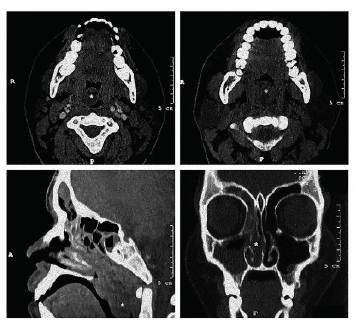

Por este hallazgo se solicitó una tomografía computarizada de cavidad bucal y senos paranasales, en la cual se definió una masa de tejido blando en la nasofaringe y fosa nasal derecha, independiente de la pared faríngea posterior (foto 2).

Los medios imagenológicos aportan importantes datos. El velamiento maxilar homolateral o la opacidad del perfil de la rinofaringe que ocupa la luz sin continuarse con la pared faríngea posterior, se puede encontrar en la proyección de Waters o Blondeau (1,2); la tomografía es más detallada al demostrar la ocupación total o parcial del seno, la continuidad con la formación endonasal y coanal 1, dimensión y la relación con las estructuras vecinas, información importante para la planificación quirúrgica 6.